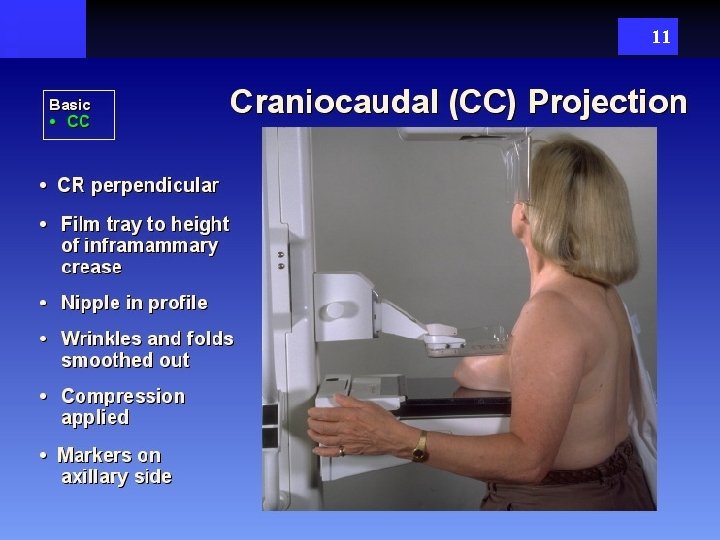

11